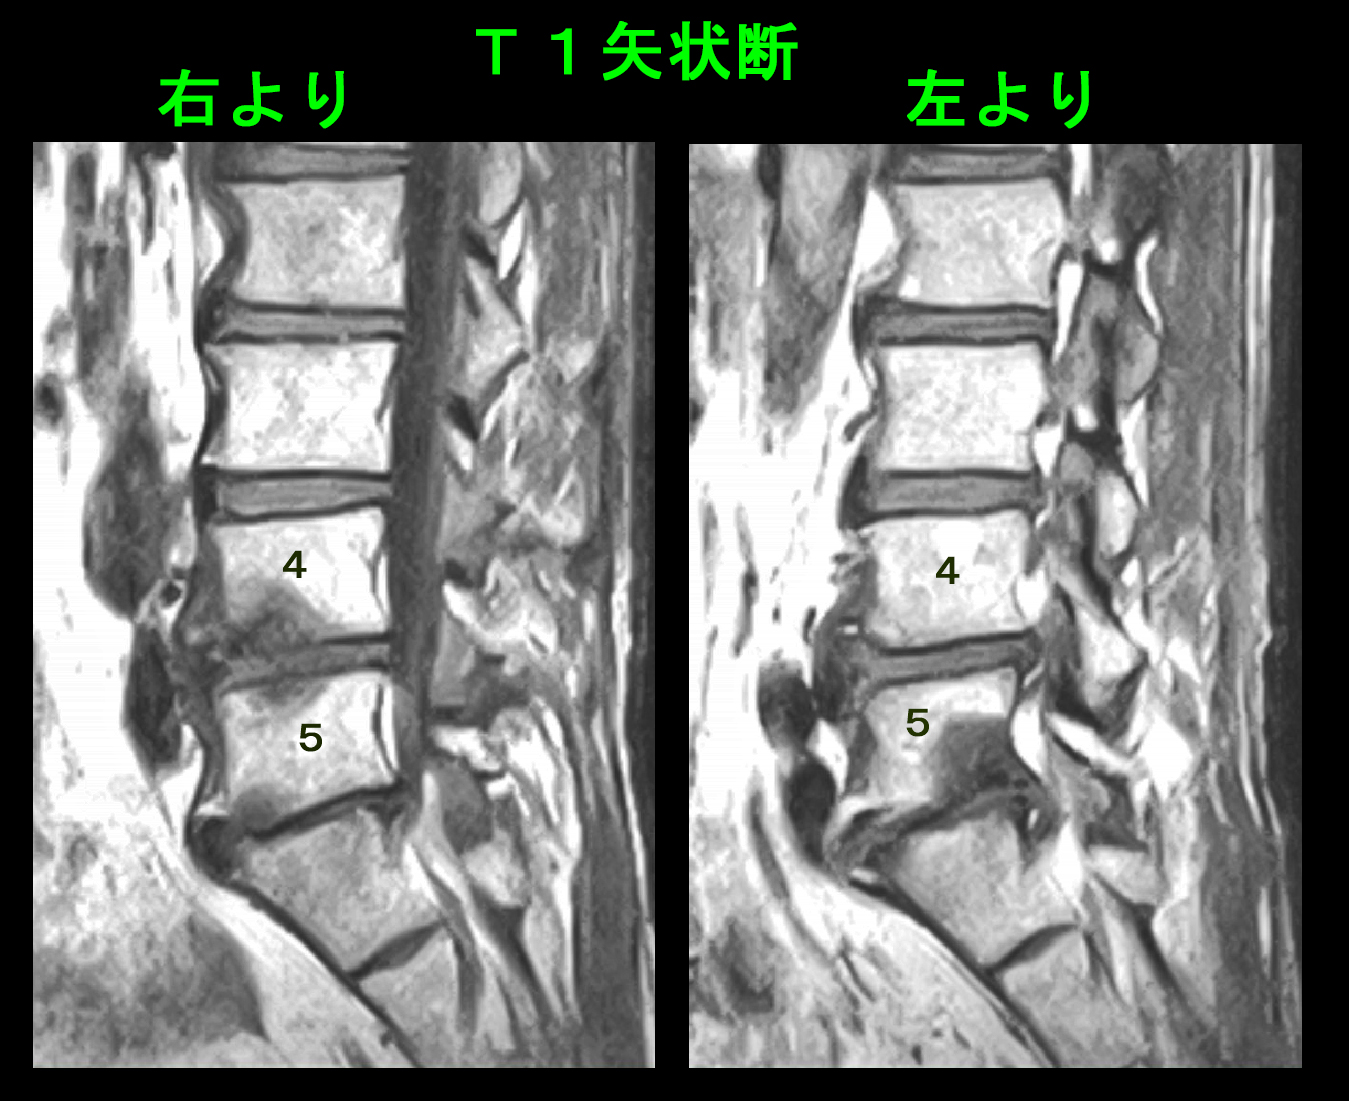

T1という条件のMRI画像では損傷を起こしている骨は黒くなりますが、L4前方下部とL5後方下部の腰骨は黒くなっています。

腹筋のトレーニングで腰を前屈させれば、L4とL5の腰骨が前方でぶつかり合うことで骨の炎症を惹起しており、背筋のトレーニングで腰を後屈させれば、L5と骨盤Sの腰骨が後方でぶつかり合って骨の炎症を起こしていて、それがVAS8の痛みの原因となっているのではないかと考えたのです。